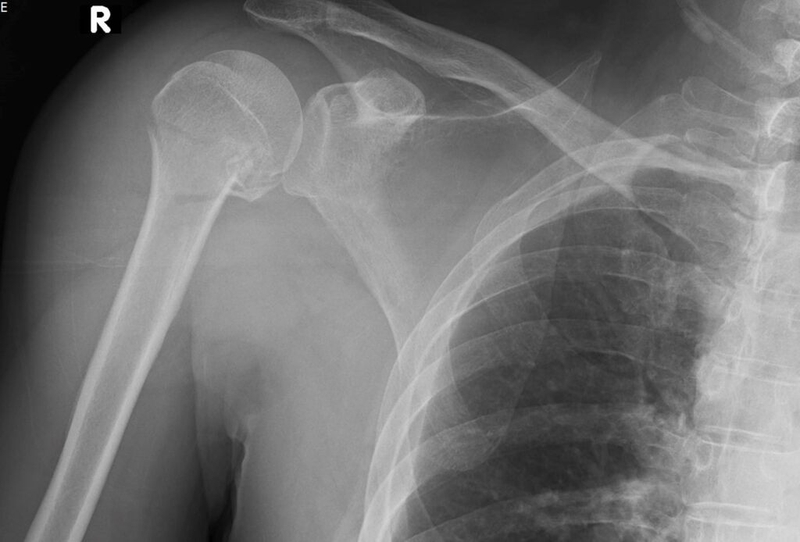

- Gãy xương đòn: Một bên xương đòn bị gãy khiến cho bên còn lại bị cong vẹo. Gãy xương như một cành cây bị gãy, một bên bị nứt còn bên kia vẫn còn nguyên vẹn.